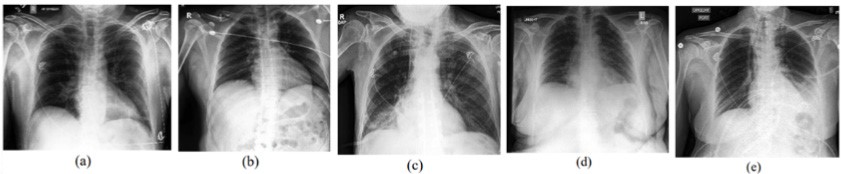

The CheXpert dataset contains 224,316 chest X-rays from 65,240 patients who underwent radiographic examination at the Stanford University Medical Center between October 2002 and July 2017. Both inpatient and outpatient X-rays are included, labeled according to the presence of 14 observations as positive, negative, or uncertain. The prediction task classifies five lung disease pathologies: atelectasis, cardiomegaly, consolidation, edema, and pleural effusion.

FIGURE 2. X-rays for each of the selected pathologies. (a) Atelectasis, (b) Cardiomegaly, (c) Consolidation, (d) Edema, (e) Pleural Effusion.